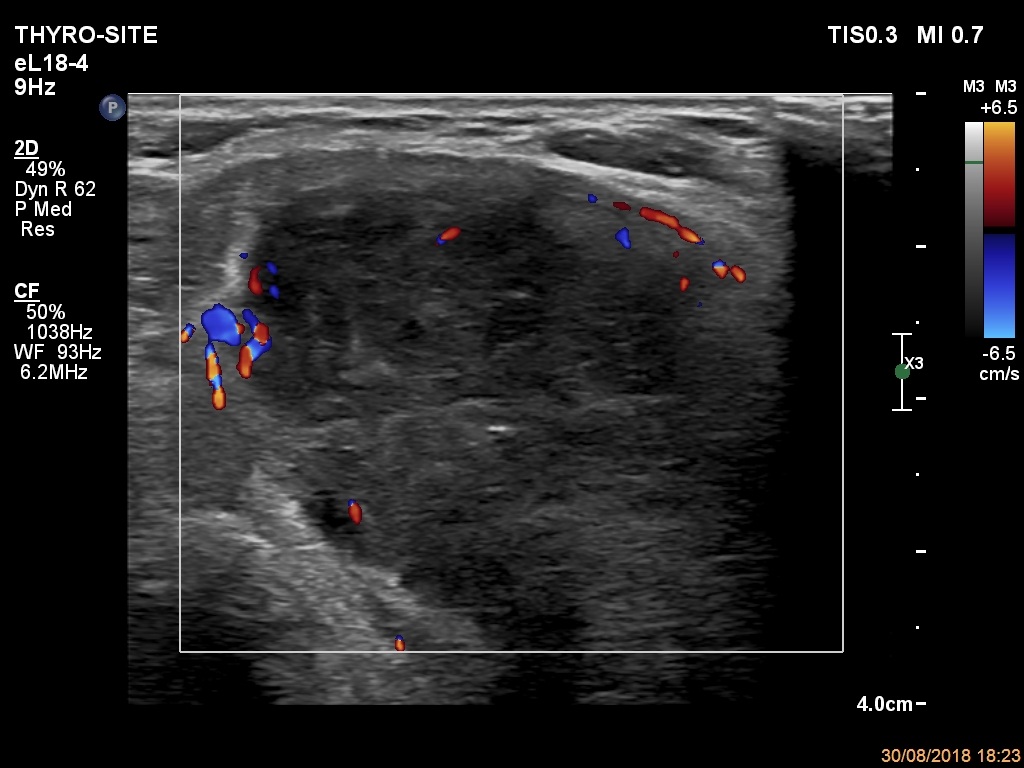

Ultrasonography. The thyroid was echonormal. There were a few hypoechogenic areas in the right lobe. There was a hypoechogenic mass with irregular shape in the left lobe. The lesion had echonormal fields and connective tissue. The microflow imaging revealed no intranodular vascularization while the lesion proved to be very hard on elastography.